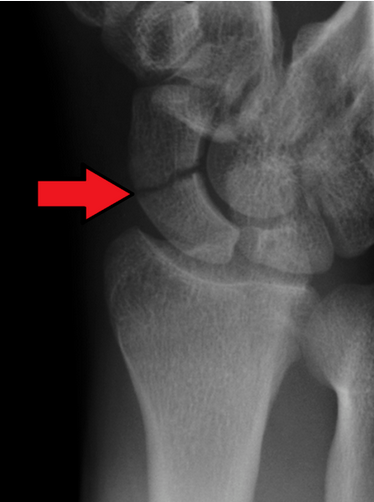

A X-ray showing a fracture through the waist of the scaphoid

The scaphoid is one of the eight small bones in the wrist called carpal bones. It is located just below the thumb and is the most commonly fractured (broken) carpal bone.

Some areas of the scaphoid have poor blood supply and may have difficulty healing and there is higher risk of avascular necrosis for scaphoid fractures.

If a scaphoid fracture is suspected, an X-ray of the wrist will be taken; however, sometimes the fracture is not seen right away.